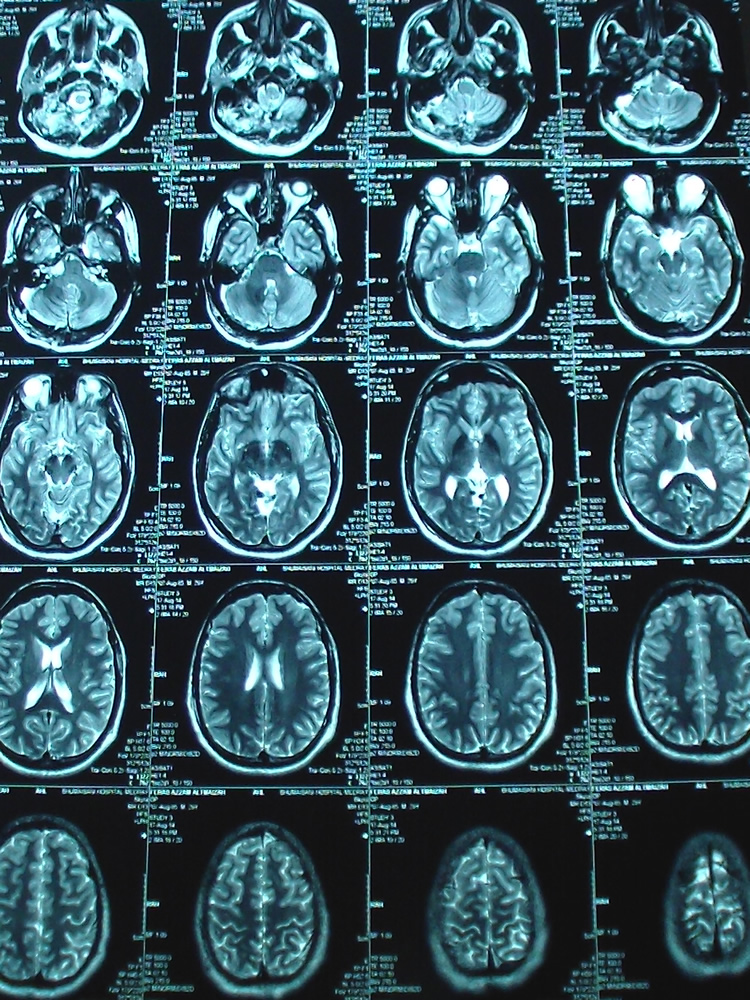

17-AUGUST-2014  FIRAS AZZAM AL-TMEZEH  29 YEARS  BILATERAL ACOUSTIC SCHWANNOMAS WITH PROGRESSING RIGHT SIDE.

The patient came to the clinic 09-January-2010 complaining of V1 pain for one month and decreased hearing right ear for 2 years. MRI of the brain performed 05-January-2010 showed right acoustic schwannoma extending to the brain stem and left intracanalicular one. Audiometry done 07-January-2010 confirming practical hearing loss in the right side. Tegretol was started and the patient came 14-April-2010 telling that he was neuralgia free with medication and the pain resumed when he stopped it. The patient was advised to keep in medication and to be followed later. The patient came 19-July-2010 with MRI of the brain done 18-July-2010 showing the same tumors sizes and the neuralgia is not present. The patient came several times over the years and he was reluctant for surgery. The last time he came 07-August-2014 and sent for new MRI which was done the same day. There is enlargement of the right acoustic schwannoma, compressing the brainstem. The right mass 25x19x17 mm  and the left 20x10x9 mm.

Figure-1: Axial TW2 done during surgery showing the removal of the residual mass which was stuck to the pontomedullary junction.

Figure-2: The intraoperative TW1 MRI showing the clearance of the right acoustic schwannoma without any edema or infarction at the resected last part f the tumor.